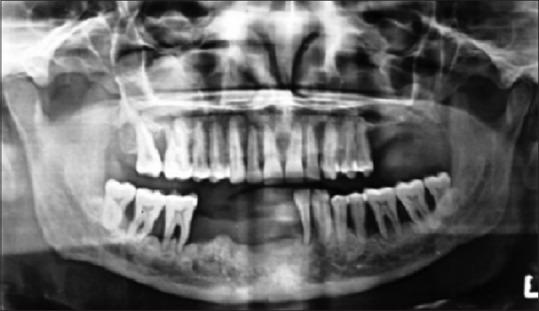

Langerhans cell histiocytosis (LCH) is a rare hematological disorder characterized by local or generalized, uncontrolled proliferation and infiltration of Langerhans type of histiocytic cells. It represents a spectrum of clinicopathologic disorders, ranging from a highly aggressive and frequently fatal multisystem disease to an easily cured solitary lesion of bone. Involvement of children and the younger age group is more common than the adults. Oral cavity involvement occurs early in LCH, but the initial symptoms are generally nonspecific, often causing misdiagnosis. This report describes a rare case of chronic localized LCH in an adult patient, with involvement of oral cavity. A 34-year-old male patient presented with multiple nodulo-papular, ulcerated lesions in gingiva involving both the jaws (primarily mandible) and the left buccal mucosa, in addition to regional teeth mobility. The most striking feature was that even after extraction of mobile teeth, the lesions persisted. After recording proper history, performing clinical and radiological evaluation, an incisional biopsy was performed followed by histopathology and immunohistochemistry to reach a confirmatory diagnosis of LCH, thereby implementing early and appropriate initiation of treatment.

摘要